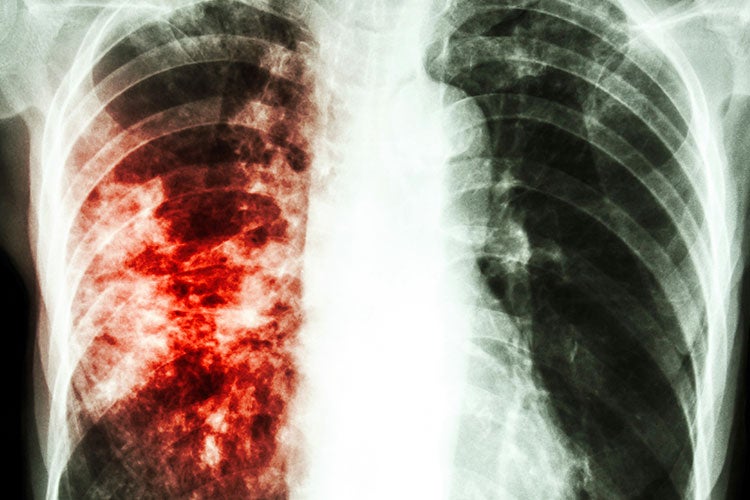

Фотографии заболеваний бронхолегочной системы